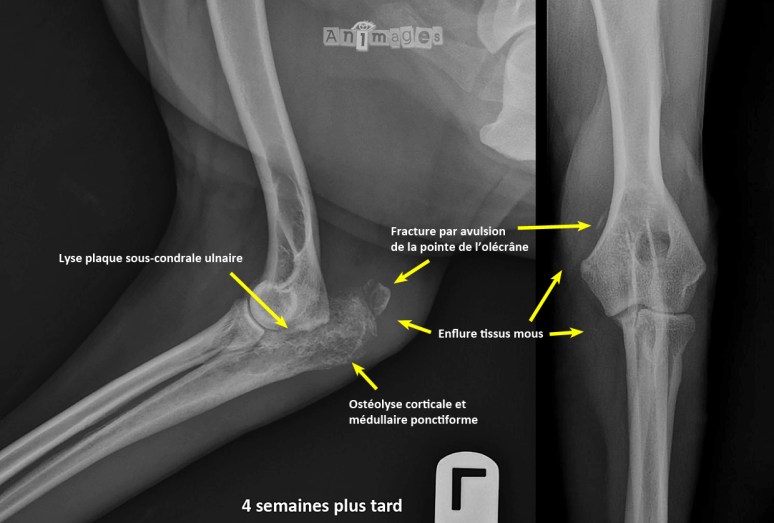

La lyse multifocale de type ponctiforme mal définie qui implique l’olécrane indique un processus agressif, comme une ostéomyélite ou encore un processus tumoral malin, tel un ostéosarcome. La localisation n’est cependant pas typique d’une tumeur osseuse primaire, tout comme l’âge et l’évolution excessivement rapide des changements radiographiques (bien que ces caractéristiques puissent aussi être rencontrées avec divers processus néoplasiques particulièrement agressifs dont les ostéosarcomes, mais aussi certaines autres tumeurs de type histiocytaire, certains hémangiosarcomes, etc.). Par ailleurs, la perte de définition de la plaque sous-chondrale ulnaire indique une composante articulaire, laquelle est plus fréquemment rencontrée lors de processus infectieux. Une cytoponction échoguidée à été réalisée pour révéler la présence d’inflammation suppurative et pyogranulomateuse, en plus d’une plénitude de levures extracellulaires d’environ 10-12 um de diamètre avec une paroi fortement basophilique, compatible avec du Blastomyces dermatitis (un fongus endémique au Québec, mais exceptionnel en France). Fugasse avait donc contracté une blastomycose qui a rapidement provoqué une ostéomyélite et une arthrite septique. La pointe de l’olécrane affaibli s’est aussi fracturée.

Malgré les essais thérapeutiques médicaux et chirurgicaux (débridement et pose d’une tige avec bande de tension et greffe osseuse), une amputation a fini par être nécessaire. Fugasse s’en est quand même tirée (mais a eu de nombreuses visites à l’hôpital pour d’autres péripéties…).